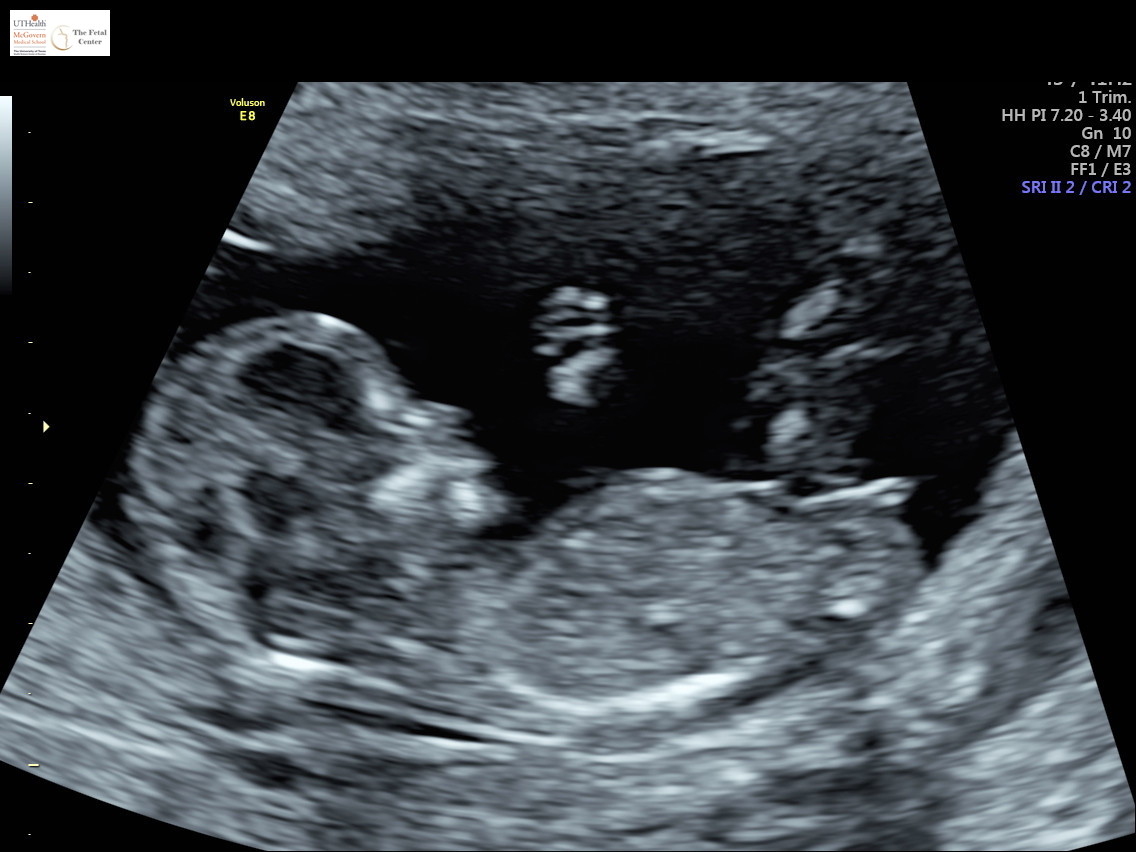

Well, my panorama test said girl but after 5 boys I'm still in disbelief. This ultrasound picture is from 12w4d. I'm now 16w3d but dont have my 20 week scan until July. I would just appreciate if any of you all would weigh in? Thanks so much!!Attachment 41669Attachment 41670